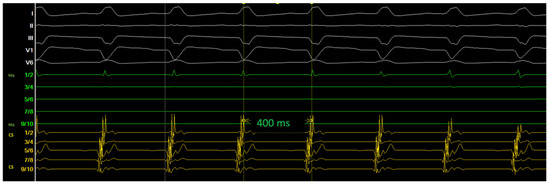

2. Method and Results

2.2. Diagnostic Workup